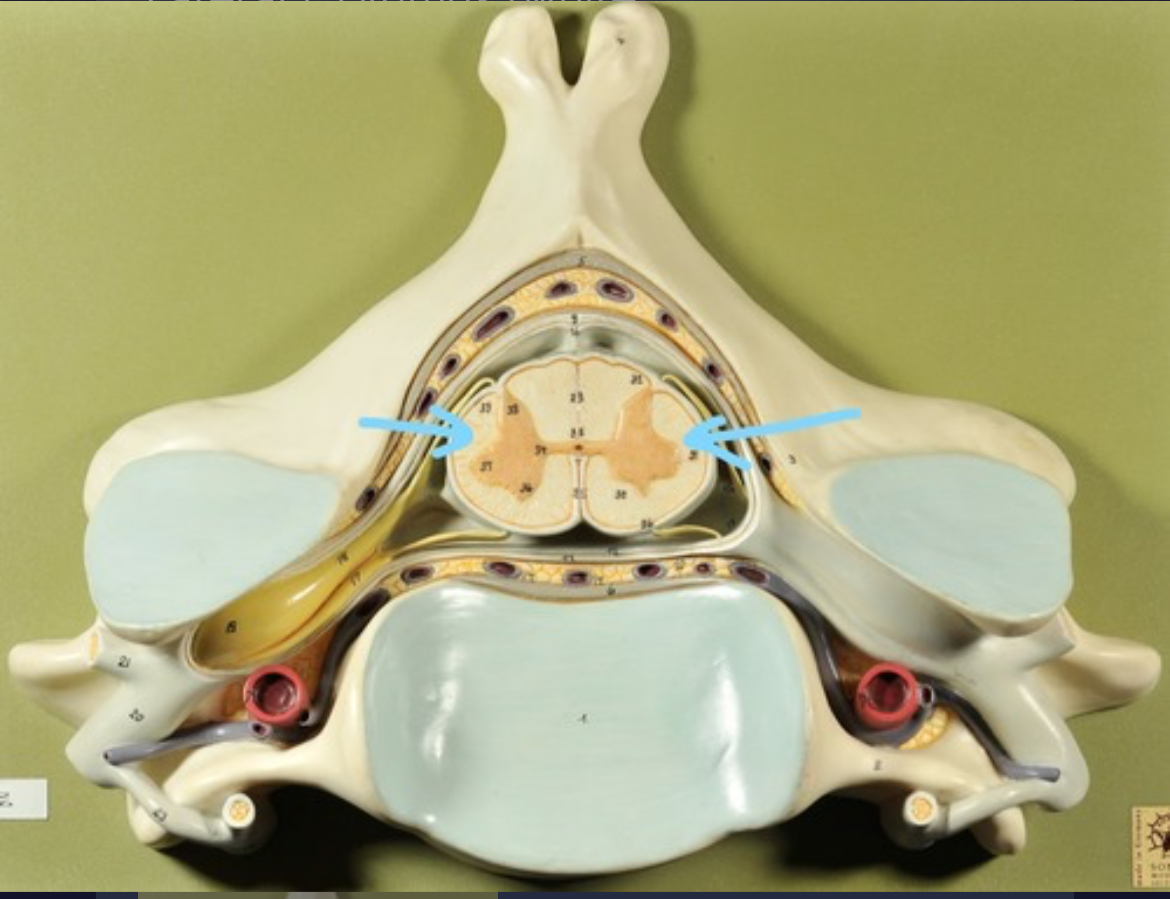

Dura mater (outermost layer)

White matter of spinal cord

Gray matter of spinal cord

Ventral horns (of gray matter)

Lateral horns

Dorsal horns

Anterior columns of white matter

Lateral columns of white matter

Posterior columns of white matter

central canal of spinal cord

Pia matter

Subarachnoid space

Arachnoid matter

Subdural space (brown line)

Dura matter

Epidural space

Dorsal root ganglion

Dorsal root

Ventral root

Spinal nerve